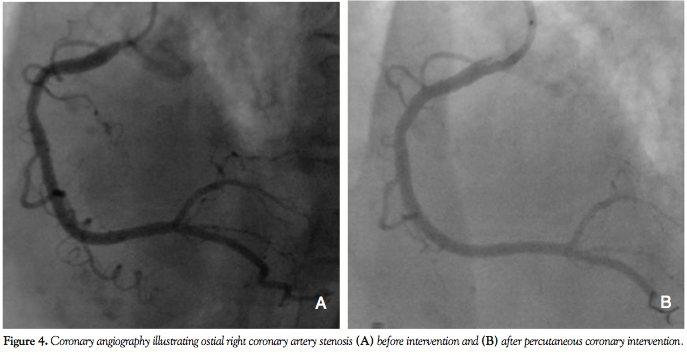

With a calculated logistic Euroscore of 25% (based on the patient’s age and sex, her presentation with an acute myocardial infarction and her critical pre-operative state), the decision was made for an invasive assessment of the coronary status with the possibility of performing PCI and TAVI in a combined percutaneous approach. The procedure was performed under conscious sedation and angiographic guidance. Coronary angiography revealed two-vessel disease, with

an 80% left circumflex artery (LCX) stenosis and an ostial 80% right coronary artery (RCA) stenosis (Figures 3A and 4A). Aortic root angiography revealed trivial aortic regurgitation and an aortic annular diameter of 24 mm, and peripheral angiography showed adequately-sized common femoral and iliac arteries with no significant stenosis or kinking. Successful percutaneous coronary intervention with implantation of two zotarolimus-eluting stents was achieved in

both the LCX and RCA (Figures 3B and 4B). Thereafter, an 18 Fr sheath was advanced into the right femoral artery under fluoroscopic guidance. The calcified stenotic aortic valve was crossed by a straight Terumo wire (Terumo, Tokyo, Japan) with the help of an Amplatz left catheter. A pigtail catheter was then advanced into the left ventricle and pressure tracings for left ventricle and aorta were simultaneously measured (Figure 5A). Then, a stiff Meier back-up wire (Boston Scientific, Natick, Massachusetts) was placed into the left ventricle and balloon aortic valvuloplasty was performed with a 22 x 60 mm Tyshak II balloon